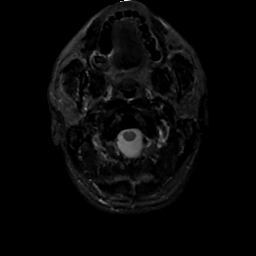

MR Study #2, February 17, 1991 -- Slice #0

[Home][Help][Clinical][Tour 1][Tour 2] Slice 0